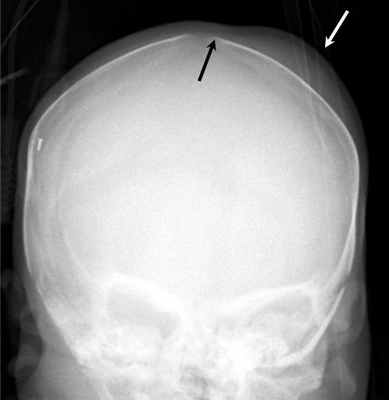

Данное отклонение от нормы представляет собой формирование излишних наслоений на поверхности теменной кости. В итоге она получается несколько толще, нежели обычно. Никаких клинических проявлений такая патология не имеет. Этим и обусловлен тот факт, что чаще всего данное отклонение от нормы становится случайной находкой в процессе проведения рентгенографии или же компьютерной томографии черепа, назначенными совсем по другим причинам.

Лечение гиперостоза не требуется. Он не только не приносит вреда здоровью, но даже не проявляется в виде косметического дефекта.